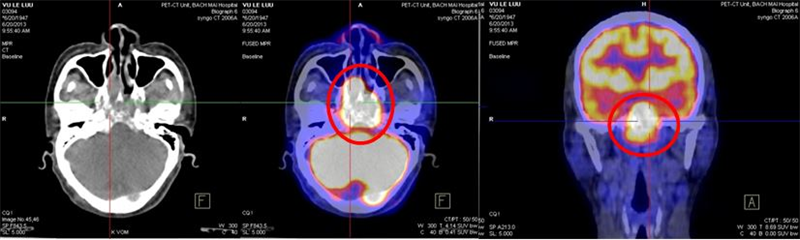

- Chụp PET/CT với 18F-FDG

Hình 3. Hình ảnh PET/CT trước điều trị: khối u vòm họng kích thước (4,5 x 6,2 x 4,3)cm, xâm lấn nền sọ tăng hấp thu FDG max SUV: 14,8 (mũi tên hoặc vòng tròn), không thấy tăng hấp thu FDG tại các vị trí khác của cơ thể.

+ Chụp PET/CT

Hình 5. Hình ảnh PET/CT sau điều trị HC: thành vòm nhẵn, không còn u. Các cơ quan bộ phận khác không thấy dấu hiệu di căn

Một số hình ảnh so sánh trước và sau điều trị HC